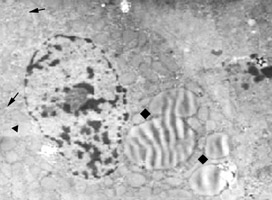

肝細胞的線粒體很多,每個細胞大約有1000個左右,遍布於胞質內。肝小葉不同部位肝細胞內線粒體的大小和形

肝細胞的線粒體在線粒體嵴的表面和內界膜的基質面上附有密集排列的、火柴頭狀的亞單位,稱為基粒。其粒由約10nm的球形頭部與寬約3.5nm、長約5nm的短柄構成。頭部伸入基質,相當於ATP合成酶所在處,是氧化磷酸化最終合成ATP酶的一部分。柄的一端與嵴的界膜相連,是一聯接蛋白,脂類和胺基酸線上粒體內被氧化成水和二氧化碳,所釋放的能量則通過這種連線蛋白轉給ADP生成ATP。線粒體的亞單位只有在特殊處理的標本中,如將線粒體由細胞勻漿中分離出來,並用低滲法破壞其界膜,使其嵴暴露,再用磷鎢酸復染,方可看到。而普通超薄切片則見不到這種亞單位,這是因為鋨酸固定時,球形頭部被解聚所致。